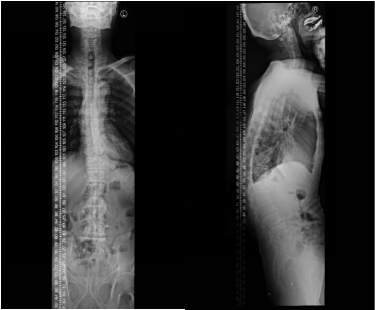

术前脊柱全长正侧位X线片

王大爷(化名),70岁,老煤矿工人,多年前已开始驼背,近几年加重,不能直站、不能躺平,稍长时间站走后,颜面就平贴地面。入院诊断为:腰椎后凸畸形,行”改良靶节段脊柱截骨矫形术”。